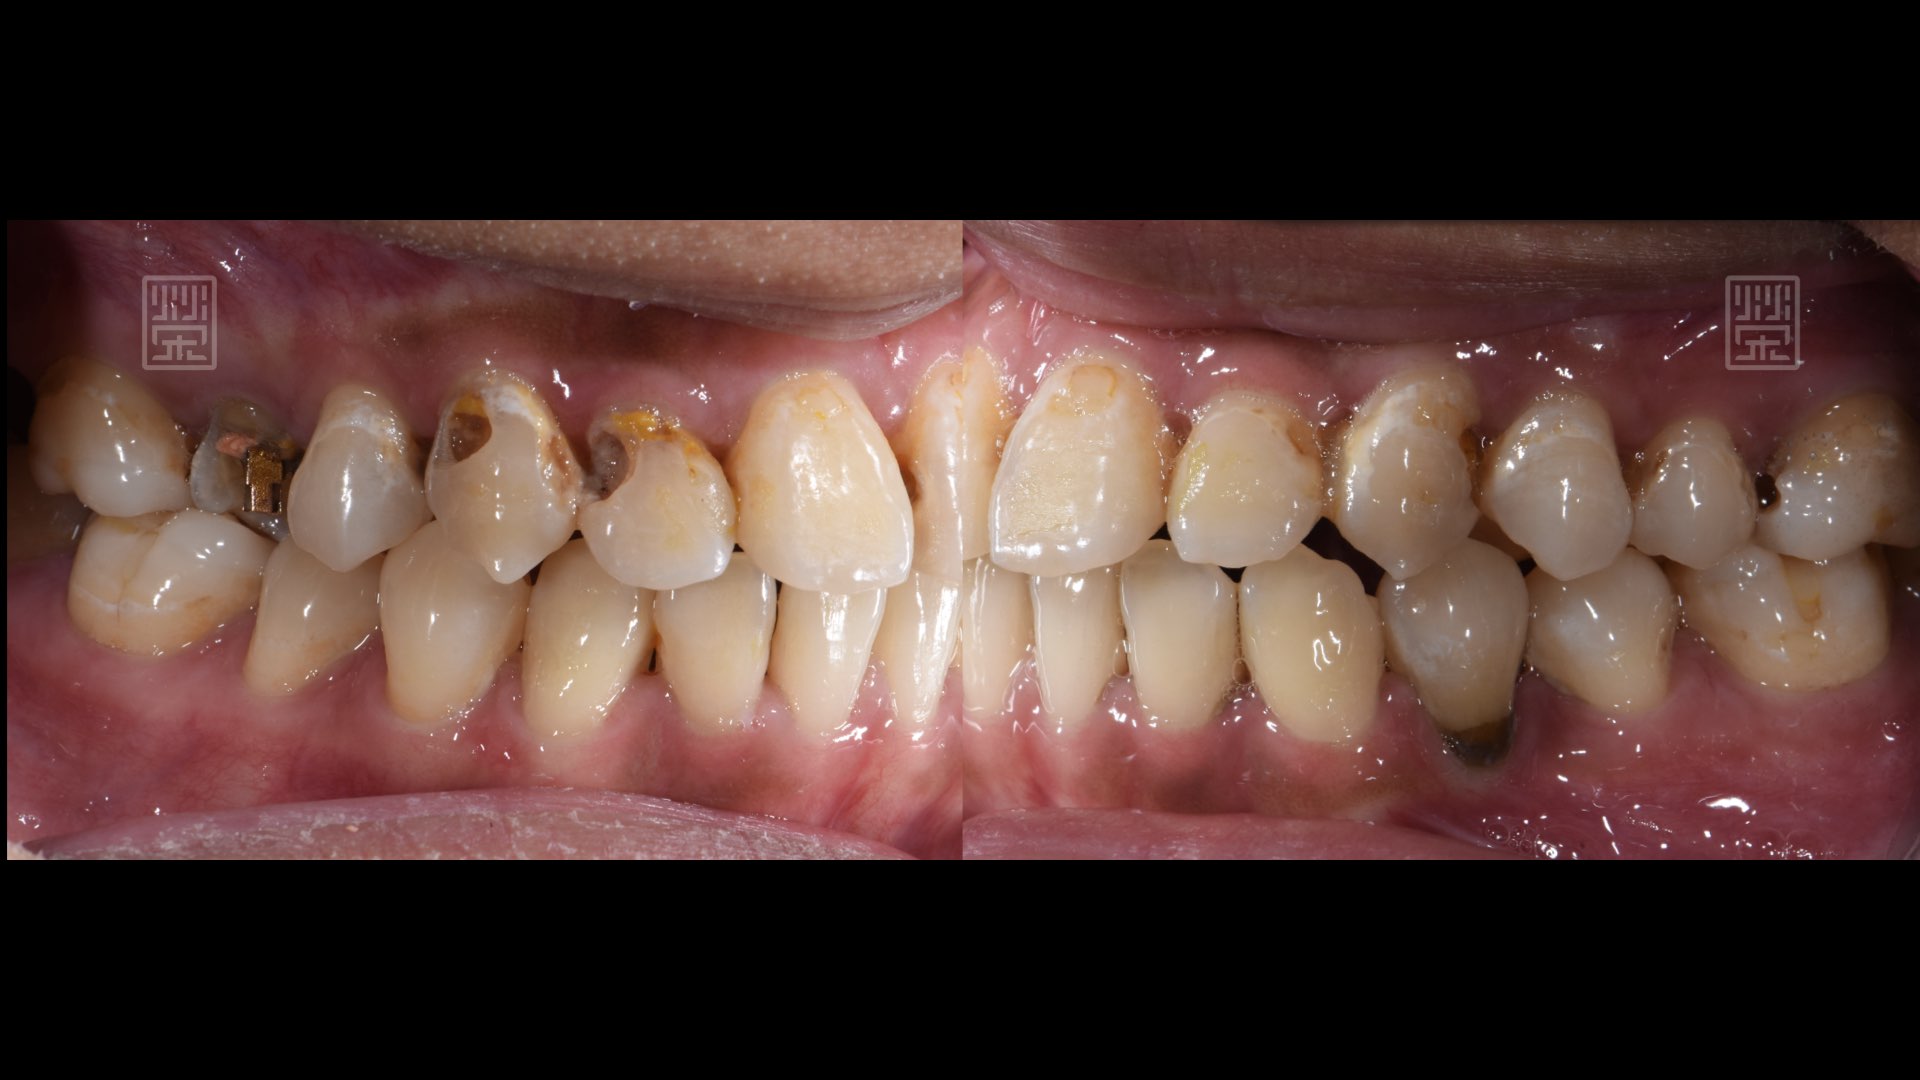

後方牙齒蛀牙斷裂

牙齒明顯蛀洞

奈米樹脂、臨時假牙修復

奈米樹脂、臨時假牙、植牙修復